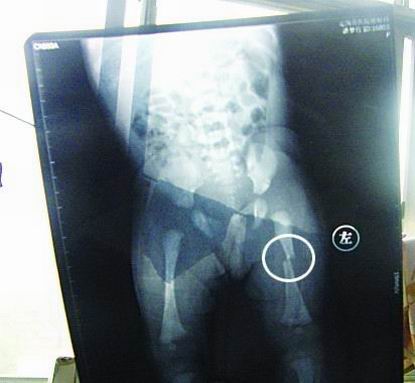

CT顯示小夢(mèng)竹左下肢骨折

今年7月2日下午,定陶縣南王店鄉(xiāng)沈莊村孕婦聶元真,在定陶縣人民醫(yī)院剖腹產(chǎn)下一女嬰,取名為潘夢(mèng)竹。醫(yī)院說(shuō),嬰兒出生后窒息,診斷為新生兒缺血缺氧性腦病,頭皮血腫。當(dāng)晚發(fā)現(xiàn)女嬰左下肢部位異常,第二天拍片顯示為左下肢骨干骨折。7月3日,潘夢(mèng)竹的頭顱CT顯示其頭頂部骨折,蛛網(wǎng)膜下腔出血,顱內(nèi)血腫。